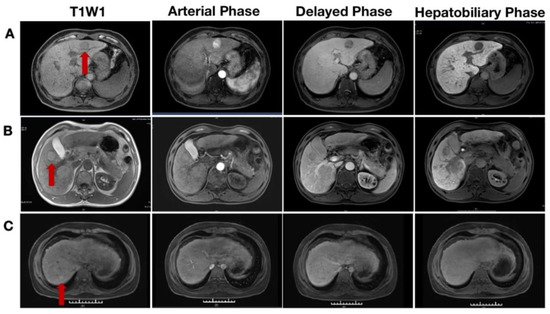

Hepatobiliary Contrast Agents